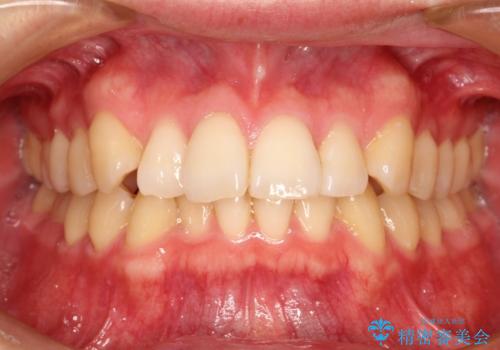

[インビザライン ライト] 短期間(3.5ヶ月)で終わるマウスピース矯正

![[インビザライン ライト] 短期間(3.5ヶ月)で終わるマウスピース矯正の症例 治療前](https://seimitsushinbi.jp/wp/wp-content/uploads/2020/02/C3-500x350.jpg?v=1580813654)